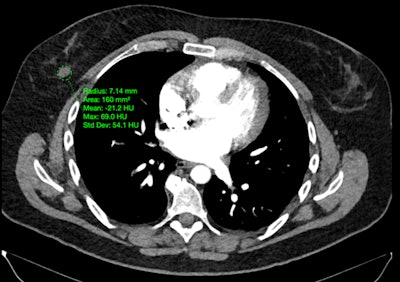

Onc.AI is a Series-A funded company that’s developing imaging AI models for predicting clinical outcomes in cancer patients, initially focusing on metastatic lung cancer.

The firm sells models directly to pharmaceutical companies such as Pfizer, GSK, and Amgen to inform drug development. It is also developing clinical models intended for medical oncology decision support.

AI predictions for treatment response in metastatic lung cancer patients are provided in a PDF format.Onc.ai

AI predictions for treatment response in metastatic lung cancer patients are provided in a PDF format.Onc.ai

“Although our AI models are solely based on a cancer patient’s CT or PET/CT scan, our main user is the medical oncologist,” said Akshay Nanduri, founder and CEO.

In January, Onc.ai received a breakthrough device designation from the U.S. Food and Drug Administration for its Onclara model for metastatic lung cancer; the software was previously known as Serial CT Response Score. The company hopes its first models will be cleared for marketing authorization as software-as-a-medical device (SaMD) decision-support software in the second half of 2026.